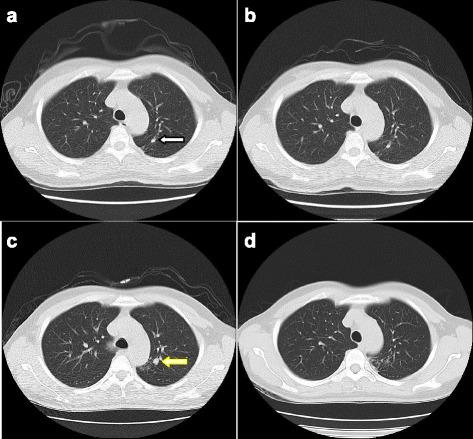

A total of 1 012 participants were included in this study. During the 4-year period of medical examinations, active PTB was found in 19 cases, and inactive PTB was found in 109 cases. The prevalence of active PTB in the participants was 1.24%, 0.67%, 0.81%, and 0.53% for years 2012 to 2015. The corresponding incidences of active PTB among the tuberculosis hospital participants were 0.86%, 0.41%, 0.54%, and 0.26%. Most HCWs with active TB (78.9%, 15/19) worked in the high-risk areas of the hospital. There was a significant difference in the incidences of active PTB between the HCWs who worked in the high-risk and non-high-risk areas (odds ratio [OR], 14.415; 95% confidence interval (CI): 4.733 - 43.896). Comparisons of the CT signs between the active and inactive groups via chi-square tests revealed that the tree-in-bud, cavity, fibrous shadow, and calcification signs exhibited significant differences (P = 0.000, 0.021, 0.001, and 0.024, respectively). Tree-in-bud and cavity opacities suggest active pulmonary tuberculosis, whereas fibrous shadow and calcification opacities are the main features of inactive pulmonary tuberculosis. Comparison with the final comprehensive diagnoses revealed that the sensitivity and positive predictive value of the diagnoses of active PTB based on LDCT alone were 100% and 86.4%, respectively.

本研究共纳入1012名参与者。在4年的体检期间,发现活动性PTB 19例,非活动性PTB 109例。2012年至2015年参与者中活动性PTB的患病率分别为1.24%、0.67%、0.81%和0.53%。结核病医院参与者中活动性PTB的相应发病率分别为0.86%、0.41%、0.54%和0.26%。大多数活动性结核病医护人员(78.9%,15/19)在医院的高风险区域工作。在高风险和非高风险区域工作的医护人员中,活动性PTB的发病率存在显著差异(优势比[OR],14.415;95%置信区间(CI):4.733 - 43.896)。通过卡方检验对活动组和非活动组的CT征象进行比较,发现树芽征、空洞、纤维影和钙化征有显著差异(P分别为0.000、0.021、0.001和0.024)。树芽征和空洞影提示活动性肺结核,而纤维影和钙化影是非活动性肺结核的主要特征。与最终综合诊断结果比较,仅基于LDCT诊断活动性PTB的灵敏度和阳性预测值分别为100%和86.4%。